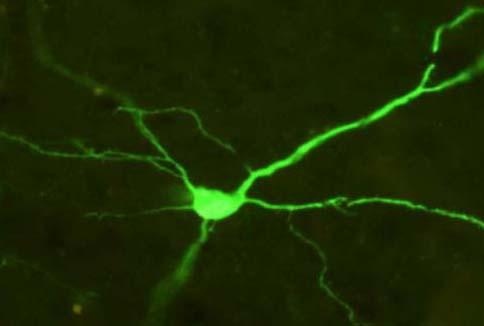

Una neurona de la corteza cerebral expresando una proteína fluorescente verde que indica la expresión exitosa de un receptor del que los autores del estudio se han valido para reproducir temporalmente en el cerebro el desequilibrio de actividad entre la corteza prefrontal y el núcleo accumbens que se da en la adolescencia. (Foto: David J. Bucci, Dartmouth College)

Para comprobar el desequilibrio causal, Meyer y Bucci utilizaron un método quimiogenético para simular el que sucede durante la adolescencia, alterando simultáneamente la actividad en la corteza prefrontal y en el núcleo accumbens. La técnica empleada permite a los investigadores “controlar remotamente” la actividad de las células cerebrales, apagando o encendiendo temporalmente células en una región durante un corto período de tiempo, inyectando para ello un virus que transfiere genes para un receptor sintético, que solo reacciona ante un fármaco sintético que también es administrado a través de una sencilla inyección.